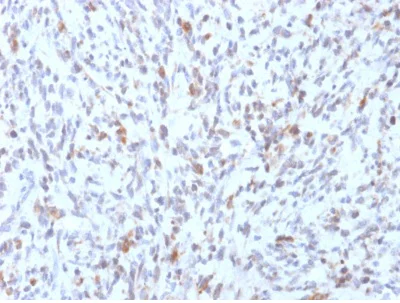

Immunohistochemistry (Formalin/PFA-fixed paraffin-embedded sections) - Anti-MyoD1 antibody [rMYD712] (AB238025)

Formalin-fixed, paraffin-embedded human Rhabdomyosarcoma tissue stained for MyoD1 using ab238025 at 2 μg/mL in immunohistochemical analysis.